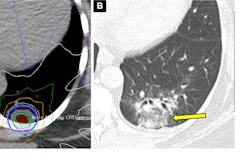

Conversely, SABR is noninvasive and involves delivering high doses of radiation with high accuracy over typically five or fewer treatment sessions. In 2021, in The Lancet Oncology, Chang and colleagues reported favorable outcomes comparing SABR with surgery after five years.

Between 2015 and 2017, 80 patients with early-stage NSCLC (<3 cm, with no lymph node involvement or distant metastasis) were recruited and underwent 15 minutes of SABR per day for three to four days as an outpatient procedure. These patients were matched with 80 patients who underwent surgery. The primary endpoint for the comparison was overall survival.